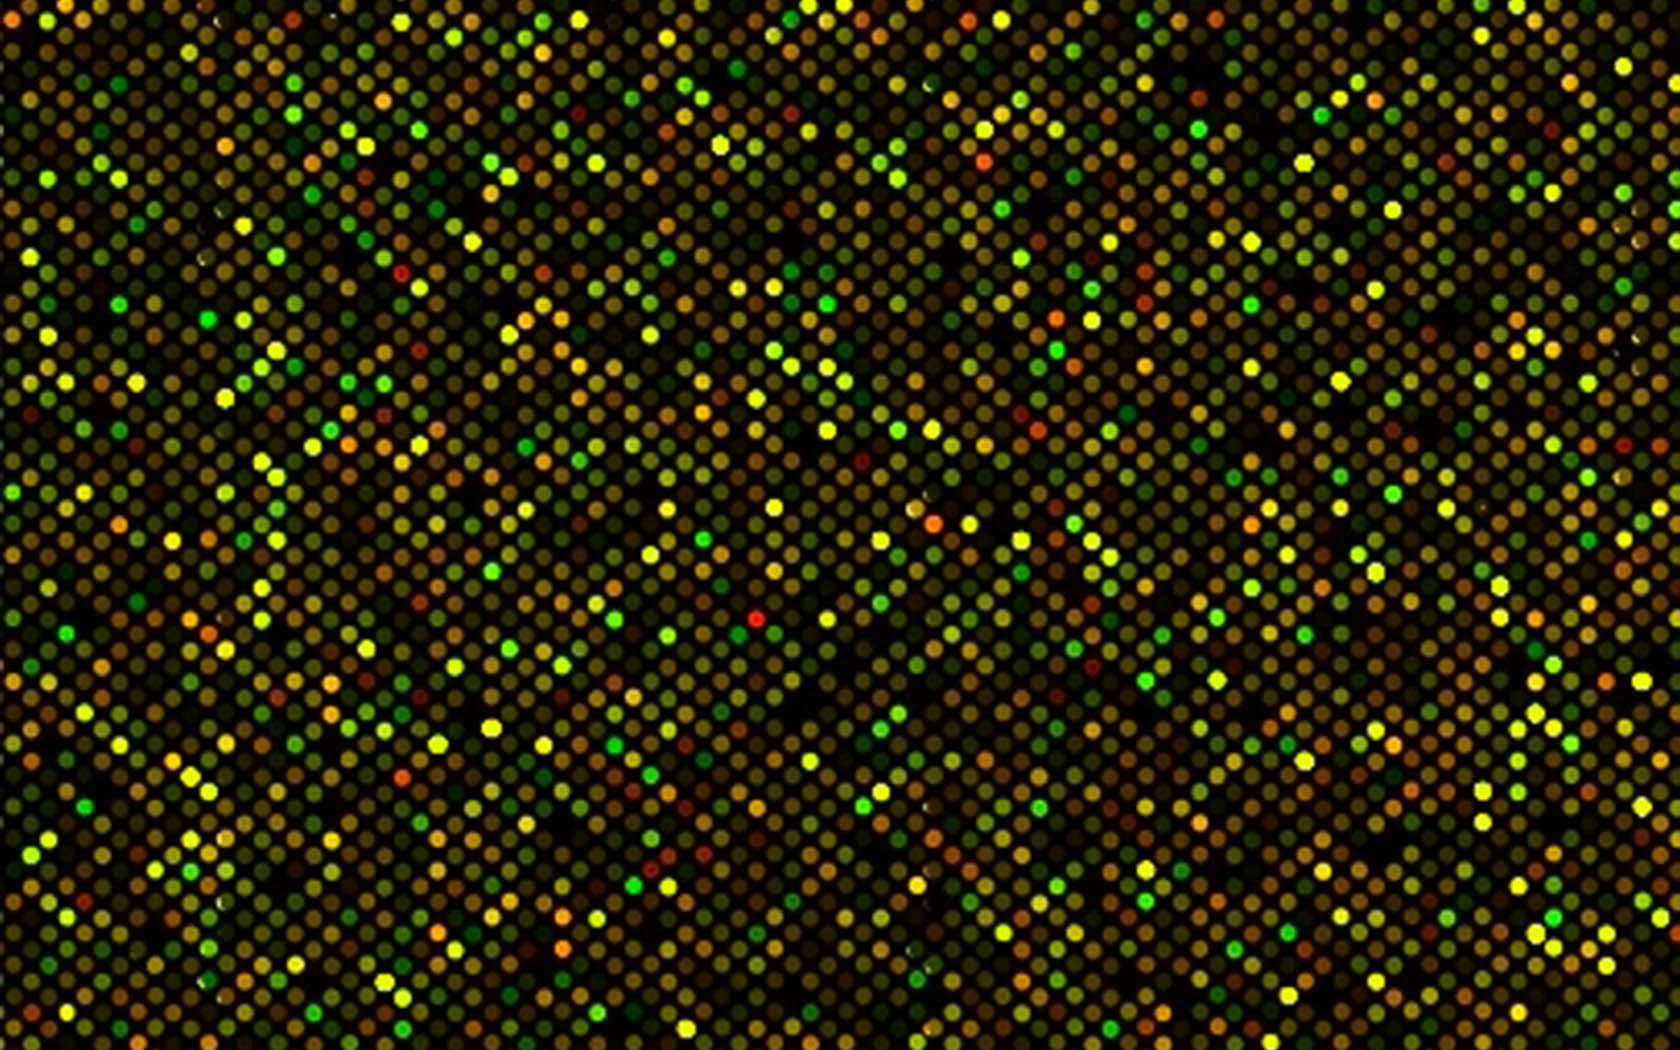

Researchers at MD Anderson are applying this same logic to cancer medicine, where tumors from patients with difficult-to-treat cancers are individually analyzed, then drugs and other therapies are prescribed to attack each tumor’s one-of-a-kind genetic and molecular makeup.

To demonstrate that this form of therapy, known as “targeted therapy” or “precision medicine,” improves outcomes in patients with advanced cancer compared to more traditional treatments, MD Anderson is conducting a randomized, controlled trial in partnership with Foundation Medicine, a Massachusetts company that provides genomic profiles to oncologists to help them match their patients to targeted therapies.

In the IMPACT1 study, researchers found that 40% of the 1,144 patients enrolled had an identifiable genomic alteration. By matching specific gene alterations to therapies, 27% of patients responded, compared to 5% with an unmatched treatment, and progression-free survival was appreciably longer in the matched group.

Foundation Medicine will provide support with their genomic profiling assay, FoundationOne, which detects all classes of genomic alterations in solid tumors across 315 cancer-related genes, as well as 28 other genes often rearranged in cancer.